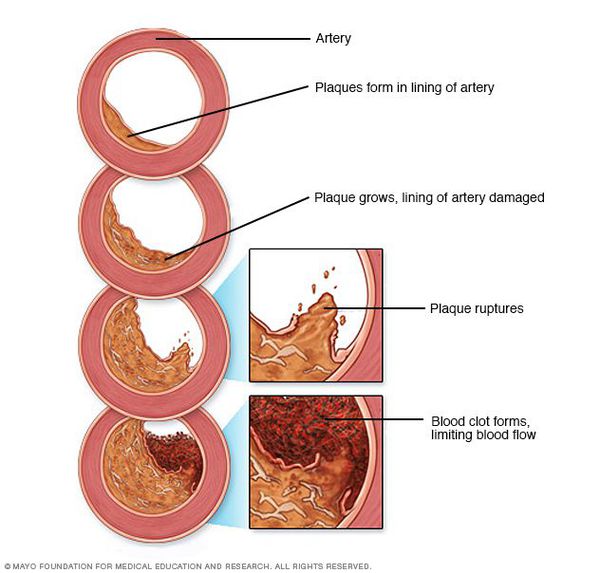

Атеросклероз — системное заболевание, первоначально поражающее сосуды, но не все, а только артерии, в стенках которых накапливается холестерин и его эфиры, образующие характерные для этого заболевания бляшки. [1]

Чем опасен атеросклероз

В дальнейшем, по мере того, как снижается способность пораженных атеросклерозом кровеносных сосудов доставлять необходимое для работы внутренних органов количество крови, поражаются и сами эти органы. Это происходит либо медленно и постепенно — в силу роста атеросклеротических бляшек, либо остро — при развитии тромбоза сосуда. Тромбоз сосудов может приводить к инфаркту миокарда, инсульту, гангрене нижней конечности.

Патогенез атеросклероза

Рост атеросклеротических бляшек — процесс, растянутый на долгие годы и десятилетия. Если бляшка в стенке сосуда достигает значительных размеров (около 70% просвета сосуда или более того), она может создавать существенные препятствия для кровотока и для кровоснабжения соответствующего органа — например, сердца или мозга. Бляшки, небольшие по размерам, тоже небезопасны — при разрыве таких бляшек (это возможно в случаях, когда истончается по разным причинам их «покрышка») в месте разрыва возникает образование тромба, который может полностью перекрыть просвет сосуда. [5] В этом случае из-за резкого ограничения кровотока возникает гибель значительного количества клеток органа, кровоснабжаемого данным сосудом — инфаркт (например, инфаркт миокарда или инфаркт мозга — инсульт, возникающий при атеросклерозе сосудов головного мозга).

Осложнения атеросклероза

В тех случаях, когда объем кровотока по пораженной артерии снижается быстро — а это происходит в случае разрыва атеросклеротической бляшки и формирования в этом участке тромба — столь же быстро развиваются симптомы, связанные с поражением соответствующего органа: инфаркт миокарда, инсульт, гангрена нижней конечности и др.